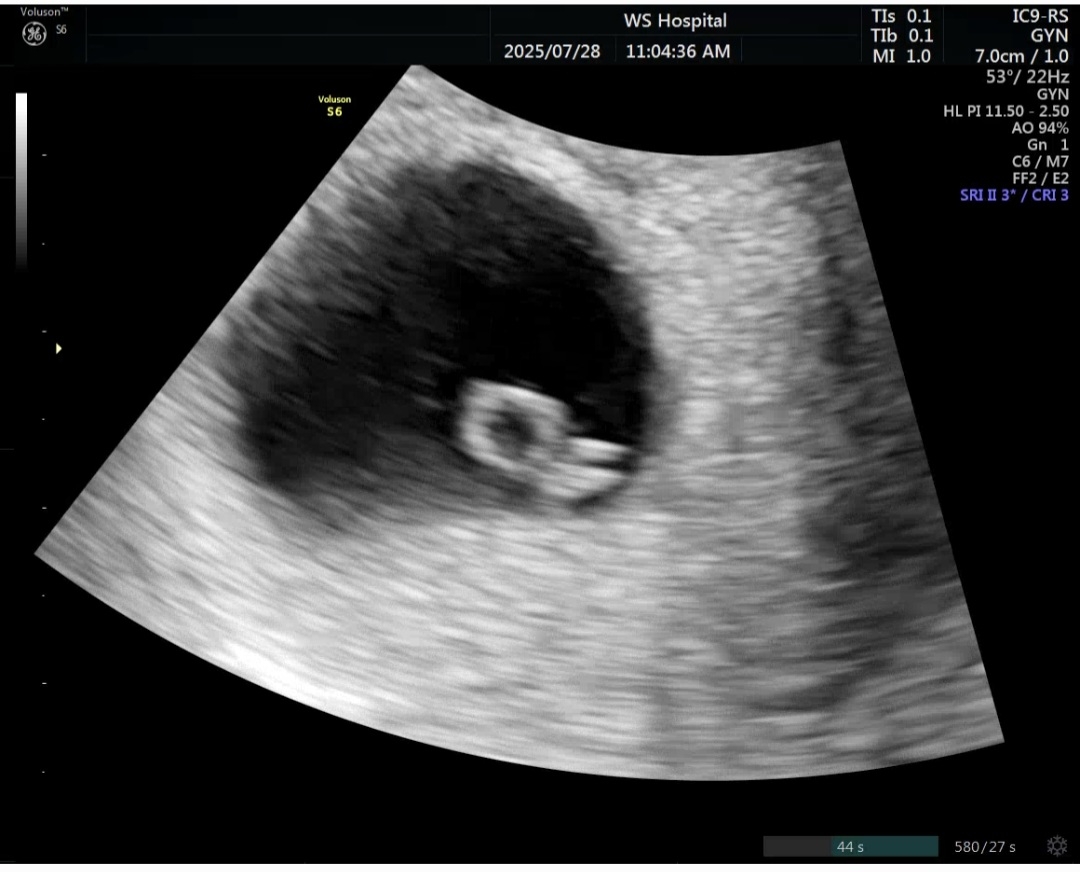

6주6일..심장이 멈췄어요

힘차게 뛰어줄거라 믿었는데.. 삼빵이도 많이 힘들었겠지.. 6주6일차..심장 반짝임도 없고.. 소리도 들리지않아요 유산이래요.. 내일 오전에 초음파 한번더 확인하고 소파술 하기로했어요.. 벌써 3번째 유산.. 너무 힘드네요..신랑도 일하다가 전화와서 엉엉 울고.. 너무속상하고 힘들어요. 언제쯤 건강하게 출산할수있을까요.. 나이도 마흔이라 걱정이 너무 많네요.. 바라는게 있다면 수술없이 자연유산으로 끝났으면 좋겠네요.. 그동안 행복했어 삼빵아..잘가 나중에는 꼭 건강하게 와줘야해